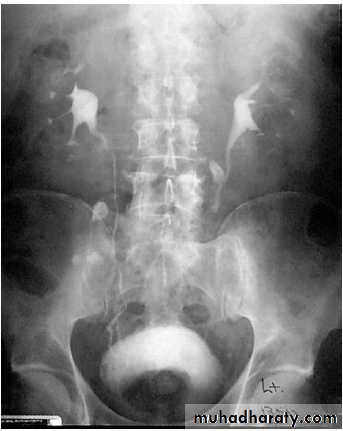

IVU: elevation of bladder base, irregular bladder out line, bladder diverticulum, fish hook lower ureter, vesical stones and residual urine.

Benign prostatic hyperplasia

Vesical stone